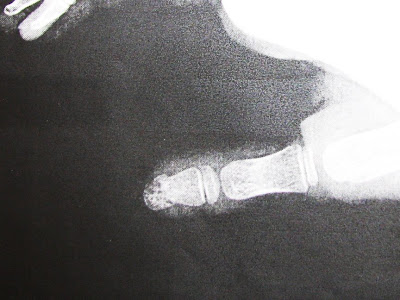

In the grand scheme of things, we have been very lucky in the kids health department. We have only had one kid with a broken bone (I however, have had two or three since we've been married- all toes and fingers) A handful of ear infections, and a few cases of rotovirus. We seem to have started a new late winter trend though. Smashed fingers.

I will warn you now. The pictures are cringe worthy.

The appointment with the Orthopedist was..... uninspiring. To be honest, I dont see why we had to go. All he did was trim Andrew's nail that was digging into the skin near the bed of this finger.